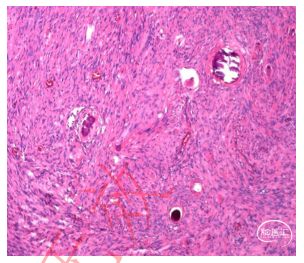

肿瘤病理